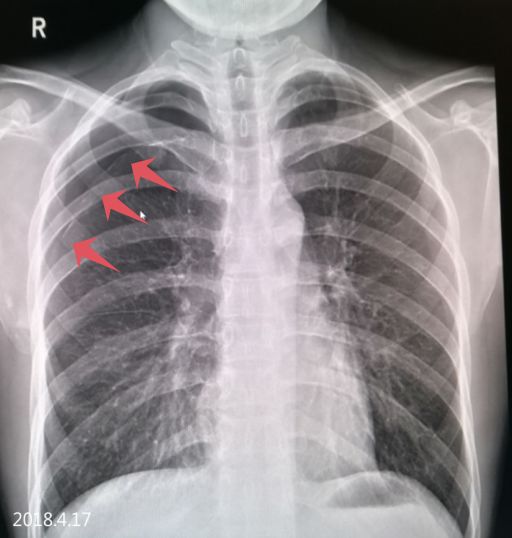

2018.4.17 气胸复张,右下肺见液平面已吸收